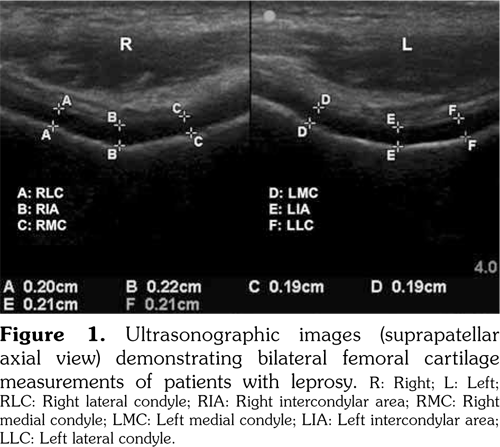

All femoral cartilage evaluations were performed by the same physician who was experienced in musculoskeletal US using a linear array probe (7-12 MHz, Sonosite M-Turbo 2007-2011, USA). Patients were assessed in supine position with their knees in maximum flexion, and the probe was placed in an axial plane on the suprapatellar area. The femoral cartilage was visualized as a strongly anechoic structure between the bony cortex and the suprapatellar fat. Three mid-point measurements were taken from each knee, at the right lateral condyle (RLC), the right intercondylar area (RIA), the right medial condyle (RMC), the left medial condyle (LMC), the left intercondylar area (LIA), and the left lateral condyle (LLC) (Figure 1).